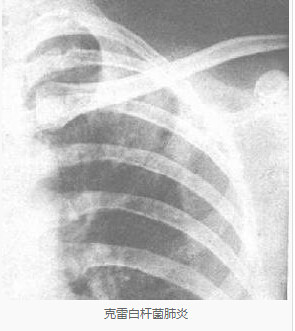

克雷白杆菌肺炎:

X线显示肺叶或小叶实变,有多发性蜂窝状肺脓肿,叶间隙下坠。